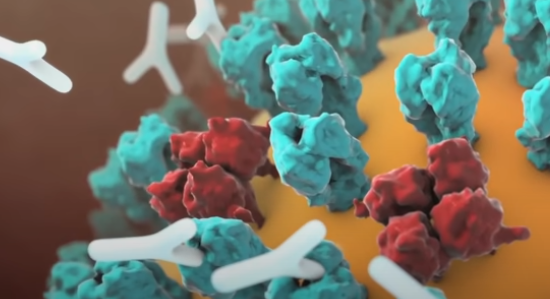

身体的免疫系统将有机会产生大量抗体来与病毒进一步战斗。而疫苗最基本的原理就是激发免疫系统生成消灭对应外来异物的抗体,或者直接给体内注射抗体。

这些抗体会识别并结合之前提到的刺突糖蛋白,防止病毒仿制出可以打开细胞大门的钥匙。

另外,这些抗体会将病毒黏连在一起,同时通知免疫细胞中的吞噬细胞来摧毁病毒,避免它在体内蔓延。